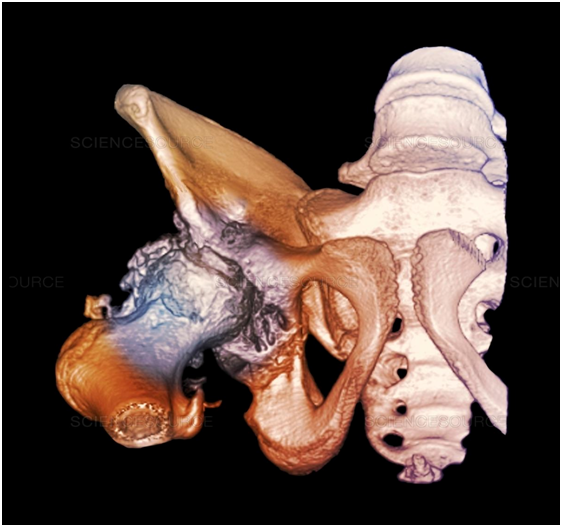

This process begins by taking a CT scan of the patient’s hip that needs replacing. Once the CT scan is received, clinical engineers can identify the bone defect and thickness after which they will run a bone loss analysis and compare those results with the patient’s healthy bone.

Once they have this information to act as a reference point, the design of the implant can begin using CAD, where factors such as the ideal center of rotation and bone preservation are taken into account for the new joint. The existing bone density as well as screw placement also must be incorporated. This only takes about one week to complete. After the design for the replacement joint is finalized, the implant is 3D printed out of metal, the most popular being highly porous titanium.